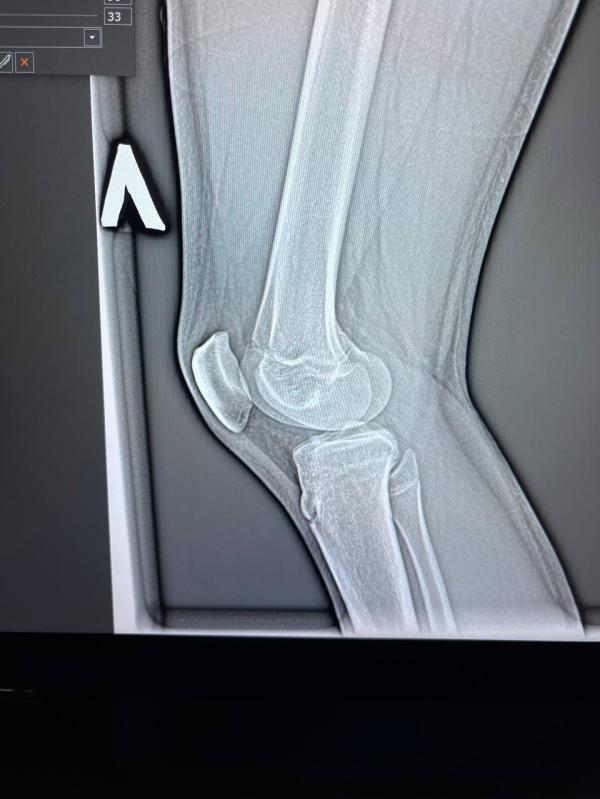

Артрит у подростка 14 лет: что видно на рентгене в 2-х проекциях?

post image 1

Неделю назад поставили артрит в 2-х проекциях, сегодня сделали рентген, кто-то разбирается ? Здесь что-то видно ?

Подросток 14 лет…